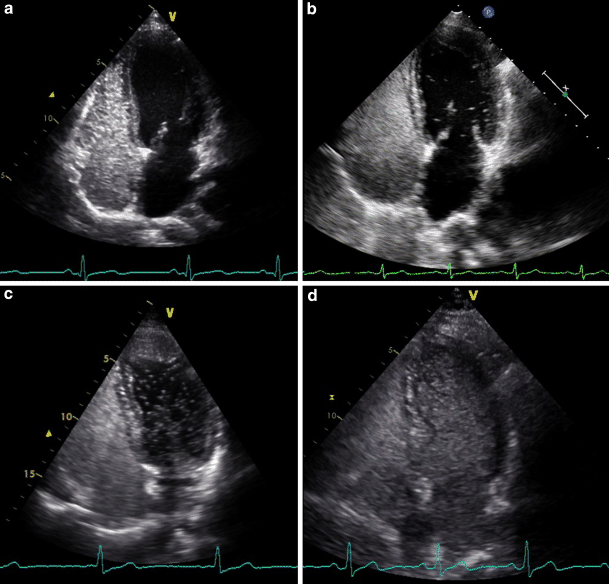

All right-to-left shunts that clearly originated out of the pulmonary vein were classified as pulmonary right-to-left shunts, and all right-to-left shunts appearing through the septum as cardiac right-to-left shunts. If shunt origin was not visible, a delay of four cardiac cycles was used to distinguish between a pulmonary and cardiac shunt. We considered the TTCE positive for a pulmonary right-to-left shunt if microbubbles appeared in the left atrium after four or more cardiac cycles. The pulmonary right-to-left shunt was graded based on the maximum number of microbubbles present in the left ventricle in one still frame. Right-to-left shunt was graded as 1, 2 or 3 corresponding with 1–29, 30–100 and over 100 microbubbles respectively (Fig. 1 and video 1–3) [3, 8, 1012].

Fig. 1

Pulmonary right-to-left shunt (RLS) on transthoracic contrast echocardiogram. a No pulmonary RLS. b Pulmonary RLS grade 1. c Pulmonary RLS grade 2. d Pulmonary RLS grade 3